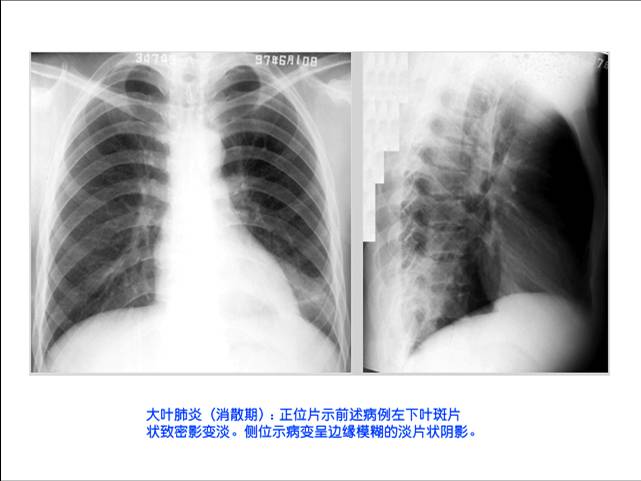

照片名称:大叶肺炎-消散期